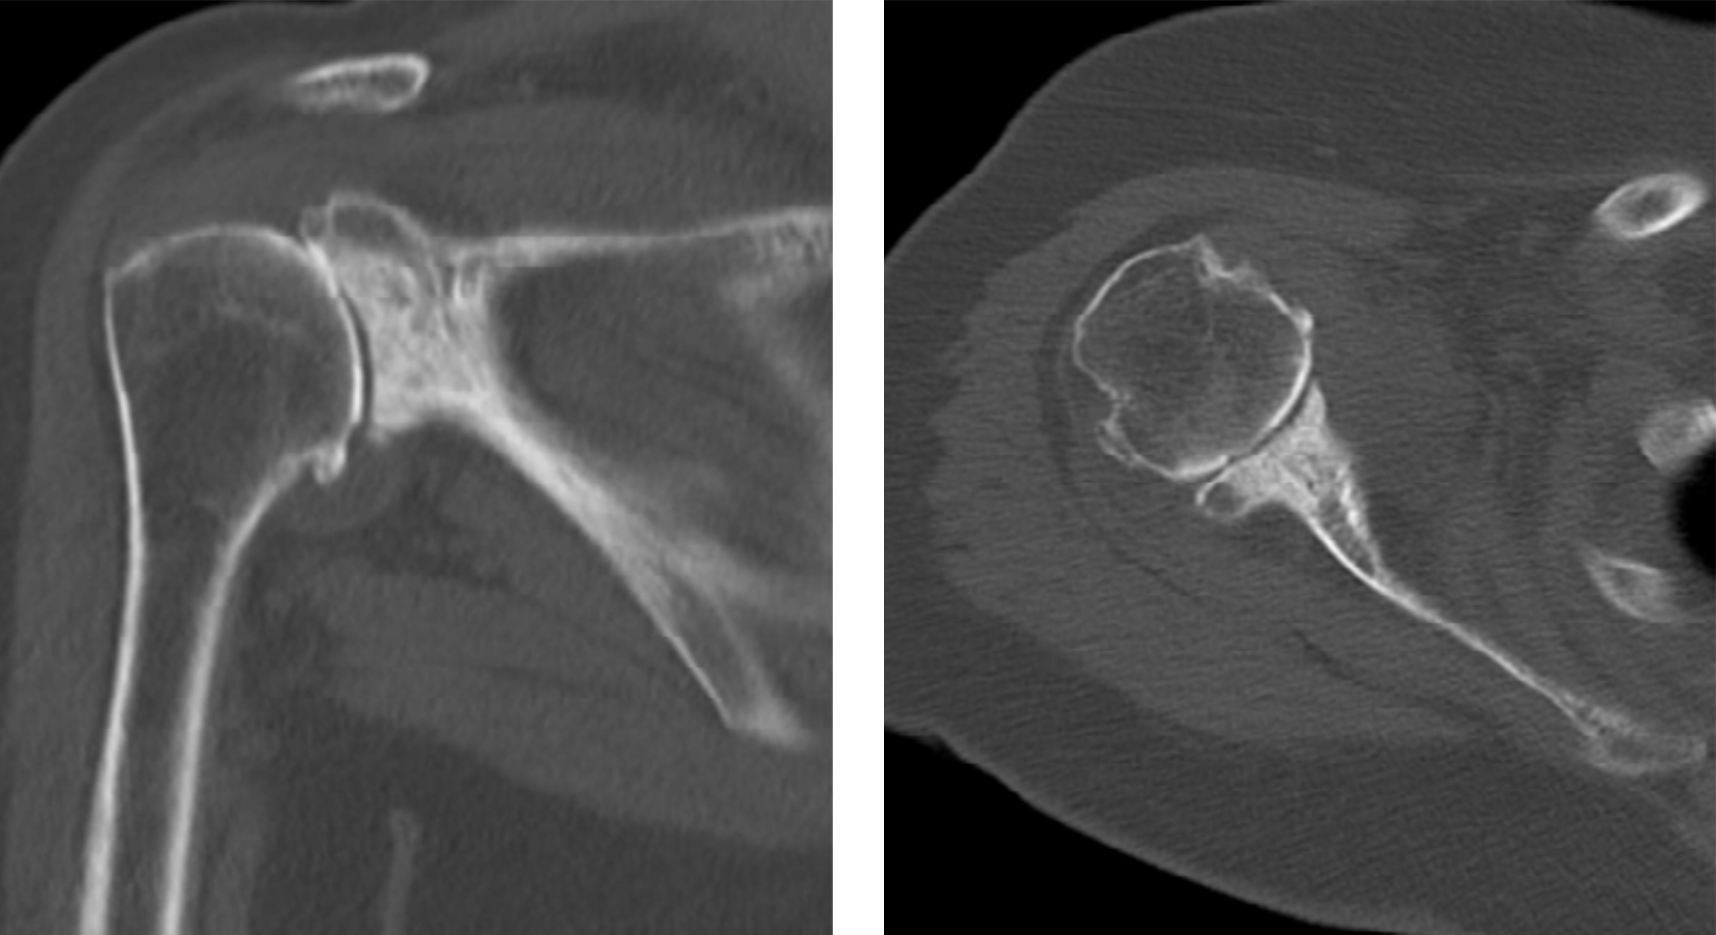

Normalmente o diagnóstico é feito através da radiografia (fig. 6) e tomografia computadorizada (para melhor determinar a versão da glenoide ou seu stock ósseo) (fig. 7) ou ressonância magnética (melhor avaliar integridade da coifa dos rotadores e infiltração gorda).